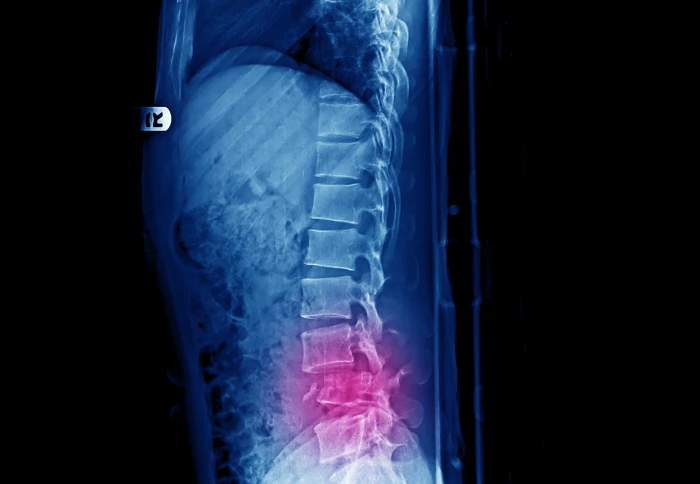

A new £7 million research project could help clinicians identify and assist patients at high risk of vertebrae fractures caused by bone tumours.

These tumours can cause vertebrae – the bones that make up the spine - to weaken and eventually fracture, leaving patients with severe pain and immobility. In some cases, the fracture can also damage the spinal cord and cause paralysis.

The researchers on the project hope that by identifying patients who are at a high risk of vertebra fracture, clinicians will be able to fit tailor-made implants to strengthen the spine and prevent the fracture.

Through developing new approaches to patient imaging and computer modelling, the researchers hope that clinicians will be able to track tumour development in the spine over time and how it may be weakening individual vertebrae.